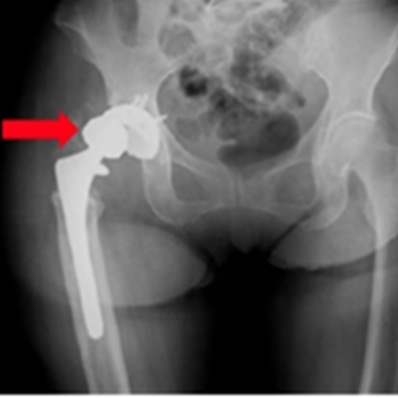

大腿骨転子部骨折

人工股関節術後脱臼